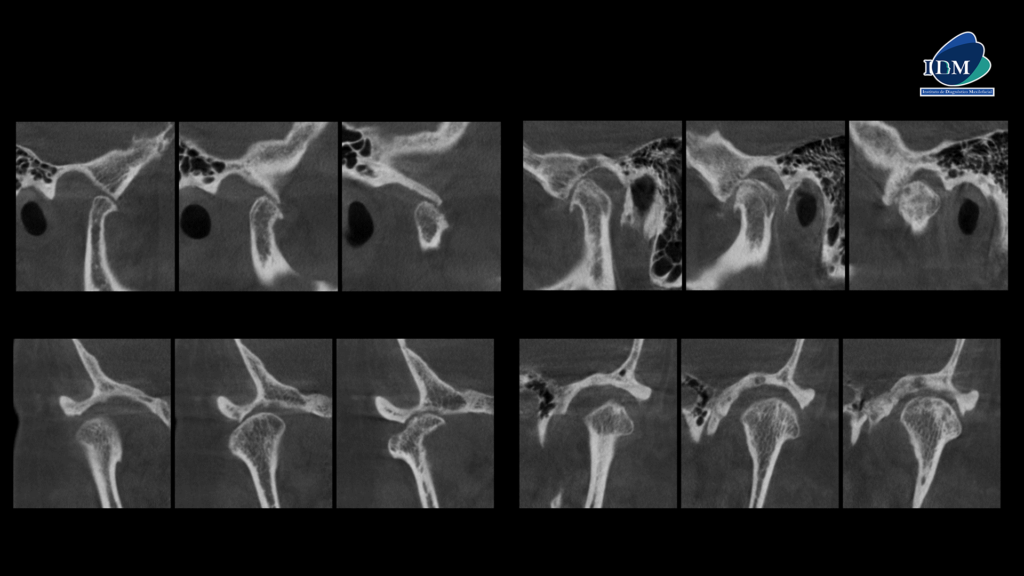

CORTES CORONALES Y SAGITALES

Así mismo en la tomografía volumétrica de haz cónico a boca abierta se evidencian osteofitos anteriores en ambos cóndilos mandibulares con disminución severa del espacio interarticular, sumado a la alteración de la morfología y estructura condilar. Finalmente, se evidencia una deformación de las vertientes de ambas eminencias articulares.